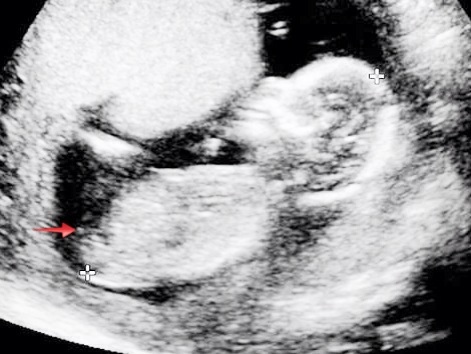

Here are my 14 week 5 day (my dates went back to normal dates) potty shots.. Tech did close up while doing scan and showed me baby had three lines and she thought it was a girl, and then said to not take that as a confirmed girl till 20 weeks!! What do you all think?

Attachment 12855